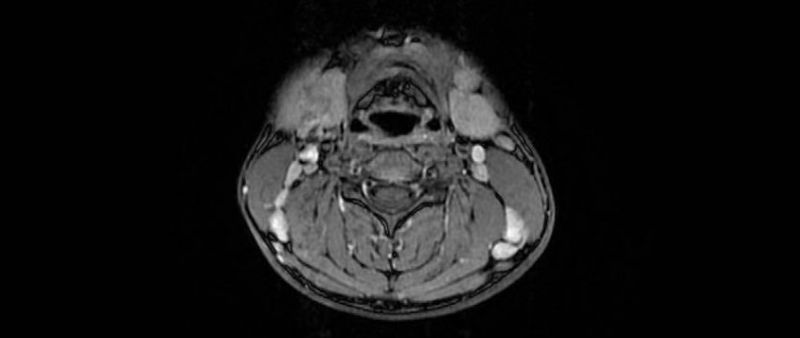

耳鼻咽喉科张月琴主任和吕超副主任医师接诊后仔细询问病史得知患者发现颈部肿物仅仅一周时间,无炎症反应,无食欲及体重的改变。查体可于颈部双侧颌下区及II、III、IV、V区触及多个肿物,质硬,活动度良好,无压痛。经过详细评估后为患者开具了颈部磁共振检查,磁共振示颈部多发淋巴结,增强扫描后可见明显强化。

至此,接诊医师根据目前的各种临床、影像诊断,初步怀疑王先生患有淋巴瘤,并向患者及家属说明病情及下一步治疗方案,建议其手术切取一个完整的肿物送病理检验明确性质。经患者及家属同意后,耳鼻咽喉科医师为王先生行全身麻醉下手术治疗,取颌下区横行切口,于右侧颌下腺表面触及大小约3*4cm肿物,与面动脉及面神经下颌缘支关系密切,经过仔细解剖后将该肿物连其包膜完整切除。术后病理示T淋巴母细胞淋巴瘤,联系血液科后转入血液科行专科治疗。